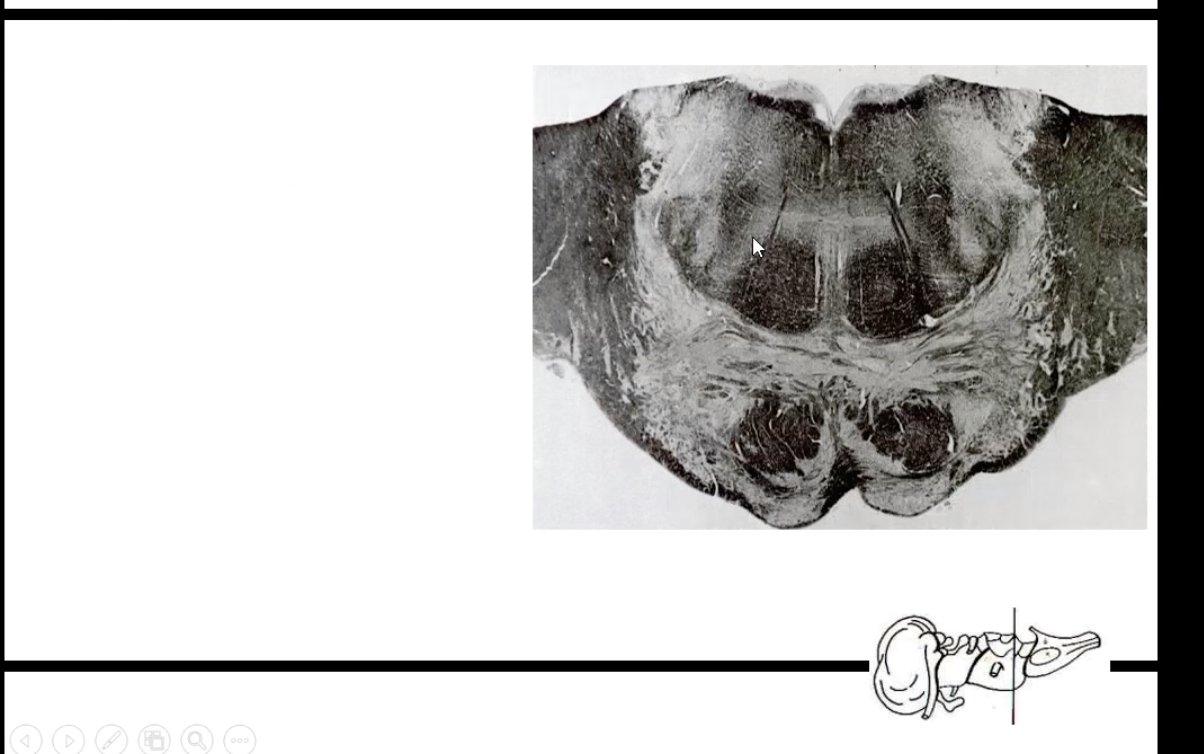

What cut is this from?

What are some characteristic of this level?

Medulla